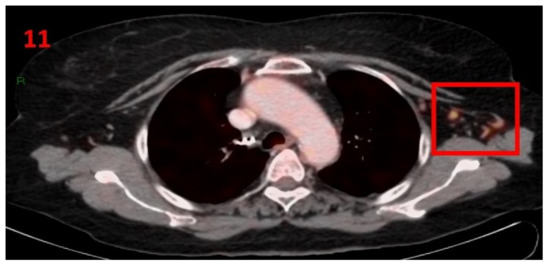

3.11. Case No 11

| Case no.11 | Uterine cervix | Left arm | 13 days | Hypermetabolic uptake in the left axillary region and lymphadenopathy | Second vaccine | 9 mm | 2.1 | Pfizer-BioNTech |